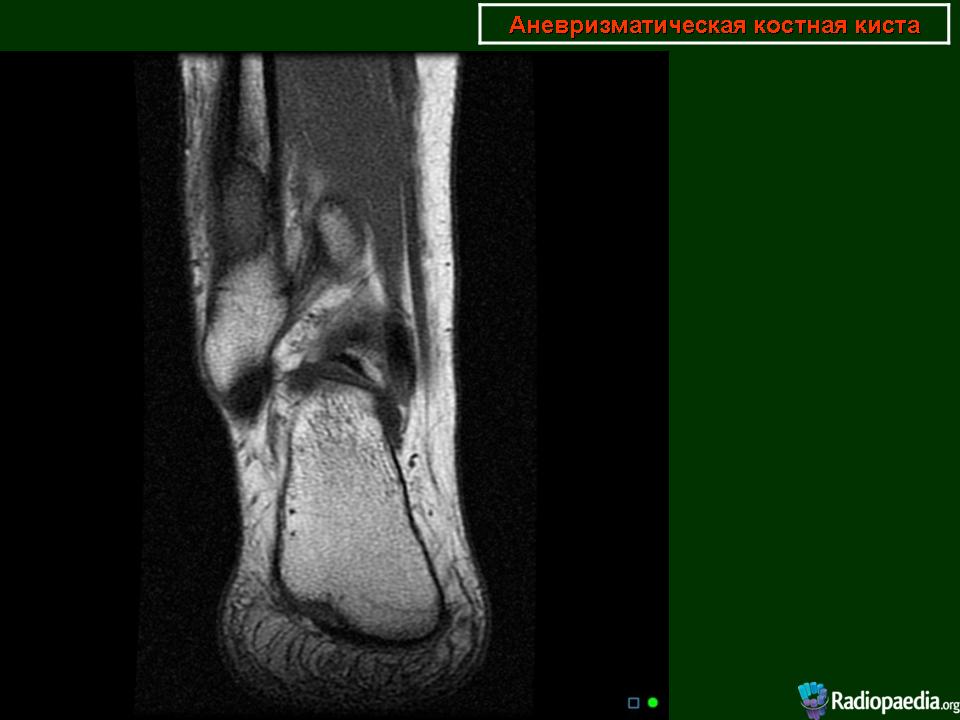

Мужчина с жалобами на периодические боли в голеностопном суставе.Спортсмен.Проходил КТ-исследование 2 года назад в Корее, принес снимки, но заключение письменного почему-то не получил.На словах сказали, что "какая-то опухоль".Его родственник -мой коллега_ попросил провести рентгенографию сустава, после чего направил на МРТ.Рентгенограммы по тех. причинам буду чуть позже))))

На отдельных изображениях, вроде создается впечатление многокомерности?

Возможно аневризматическая киста...

По поводу случая-пока склоняюсь к аневризматической костной кисте.Может быть и неправа, но узнаю результаты похода пациента в онкодиспансер.

Я за кисту. Но на МРТ не нравиться , что процесс выходит за пределы кости.